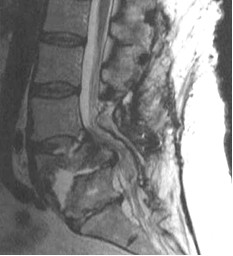

Przedstawione poniżej profilowe badanie dolnego odcinka kręgosłupa MRI (T1) dotyczy chorej leczonej uprzednio z powodu objawowego ostrego ropniaka nadtwardówkowego za pomocą laminektomii L5-S1. Zachowawcze leczenie antybiotykoterapią celowaną nie doprowadziło do ustąpienia procesu ropnego trzonów L5-S1 prowadząc do ich znaczącej destrukcji. Klinicznie zespół bólowy oraz objawy neurologiczne dysfunkcji ogona końskiego. Podaj jakie jest optymalne postępowanie chirurgiczne na tym etapie leczenia?

1) ortoza zewnętrzna i kontynuowanie celowanego leczenia zachowawczego;

2) szerokie odbarczenie tylne i tylna stabilizacja przy pomocy przeszczepów kostnych;

3) usunięcie resztek trzonów, stabilizacja przednia przy pomocy implantu koszyka i własnego, uszypułowanego przeszczepu kostnego;

4) wyłącznie celowana antybiotykoterapia, drenaż przepływowy i unieruchomienie;

5) wielopoziomowa instrumentalna stabilizacja tylna z przeszczepem kostnym.

Pytanie 10